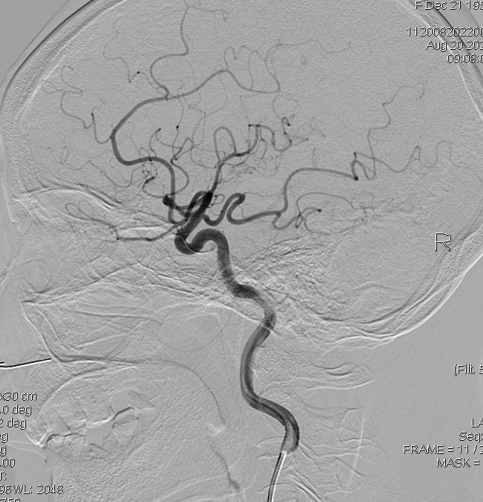

DSA显示右侧大脑中动脉分支减少: